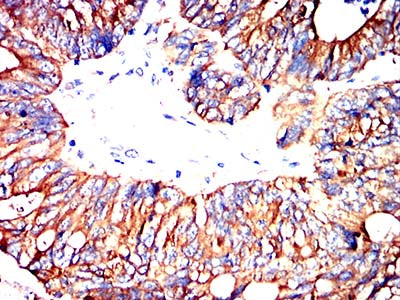

Immunohistochemical analysis of paraffin-embedded human lung cancer tissues using MRP3 mouse mAb with DAB staining.